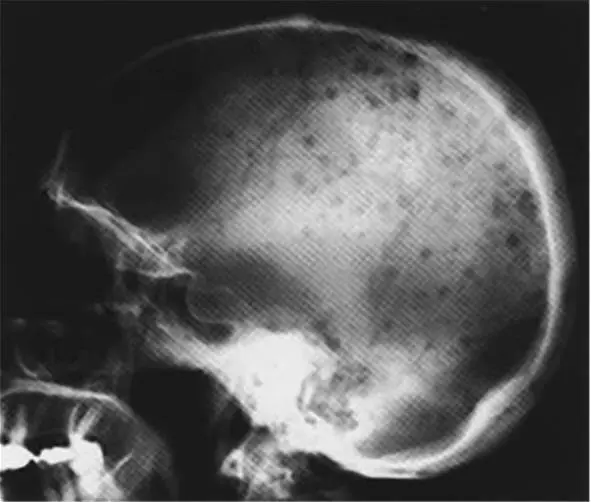

Рентгенологическое исследование скелета у больных множественной миеломой может выявить единичные или множественные очаги остеолиза в черепе, ребрах, лопатках, позвоночнике и подвздошных костях (рис. 5.30). Более эффективно поражение позвоночника регистрируется с помощью ядерно-магнитного резонанса .

Рис. 5.30. Рентгенограмма черепа больного с ММ, иллюстрирующая многочисленные очаги деструкции